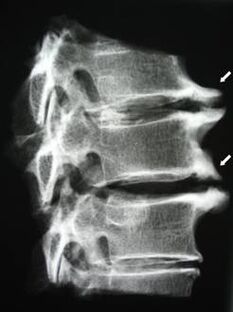

Im Anfangsstadium wird Osteochondrose mittels MRT erkannt. Später kann die Pathologie mithilfe der Radiographie diagnostiziert werden. Auf Röntgenaufnahmen der Halswirbelsäule machen sich eine Verringerung des Wirbelabstands, pathologische Veränderungen der Facettengelenke und Osteophytose bemerkbar.

| Zervikale Osteochondrose | Das Auftreten pathologischer Veränderungen in einem oder mehreren Bewegungssegmenten der Wirbelsäule. Beeinträchtigte Beweglichkeit der Wirbelsäule, Entwicklung myofaszialer Schmerzsyndrome und Einklemmen der Wirbelsäulenwurzeln | Schmerzen, Parästhesien und motorische Störungen im Halsbereich, die sich auf den Hinterkopf und die oberen Gliedmaßen ausbreiten. Erkennung charakteristischer Veränderungen der Wirbelsäule im MRT und im Röntgenbild (Osteophyten, verringerter Wirbelabstand, Anzeichen einer Schädigung der Zwischenwirbelgelenke) |